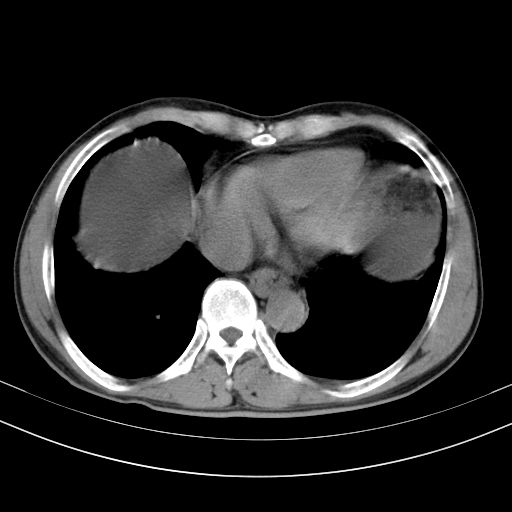

以下是引用随光逐影在2010-2-28 10:23:00的发言:[br]1)考虑肝癌;建议行ct增强扫描检查。2)肝硬化,脾大,腹水。3)慢性胆囊炎。